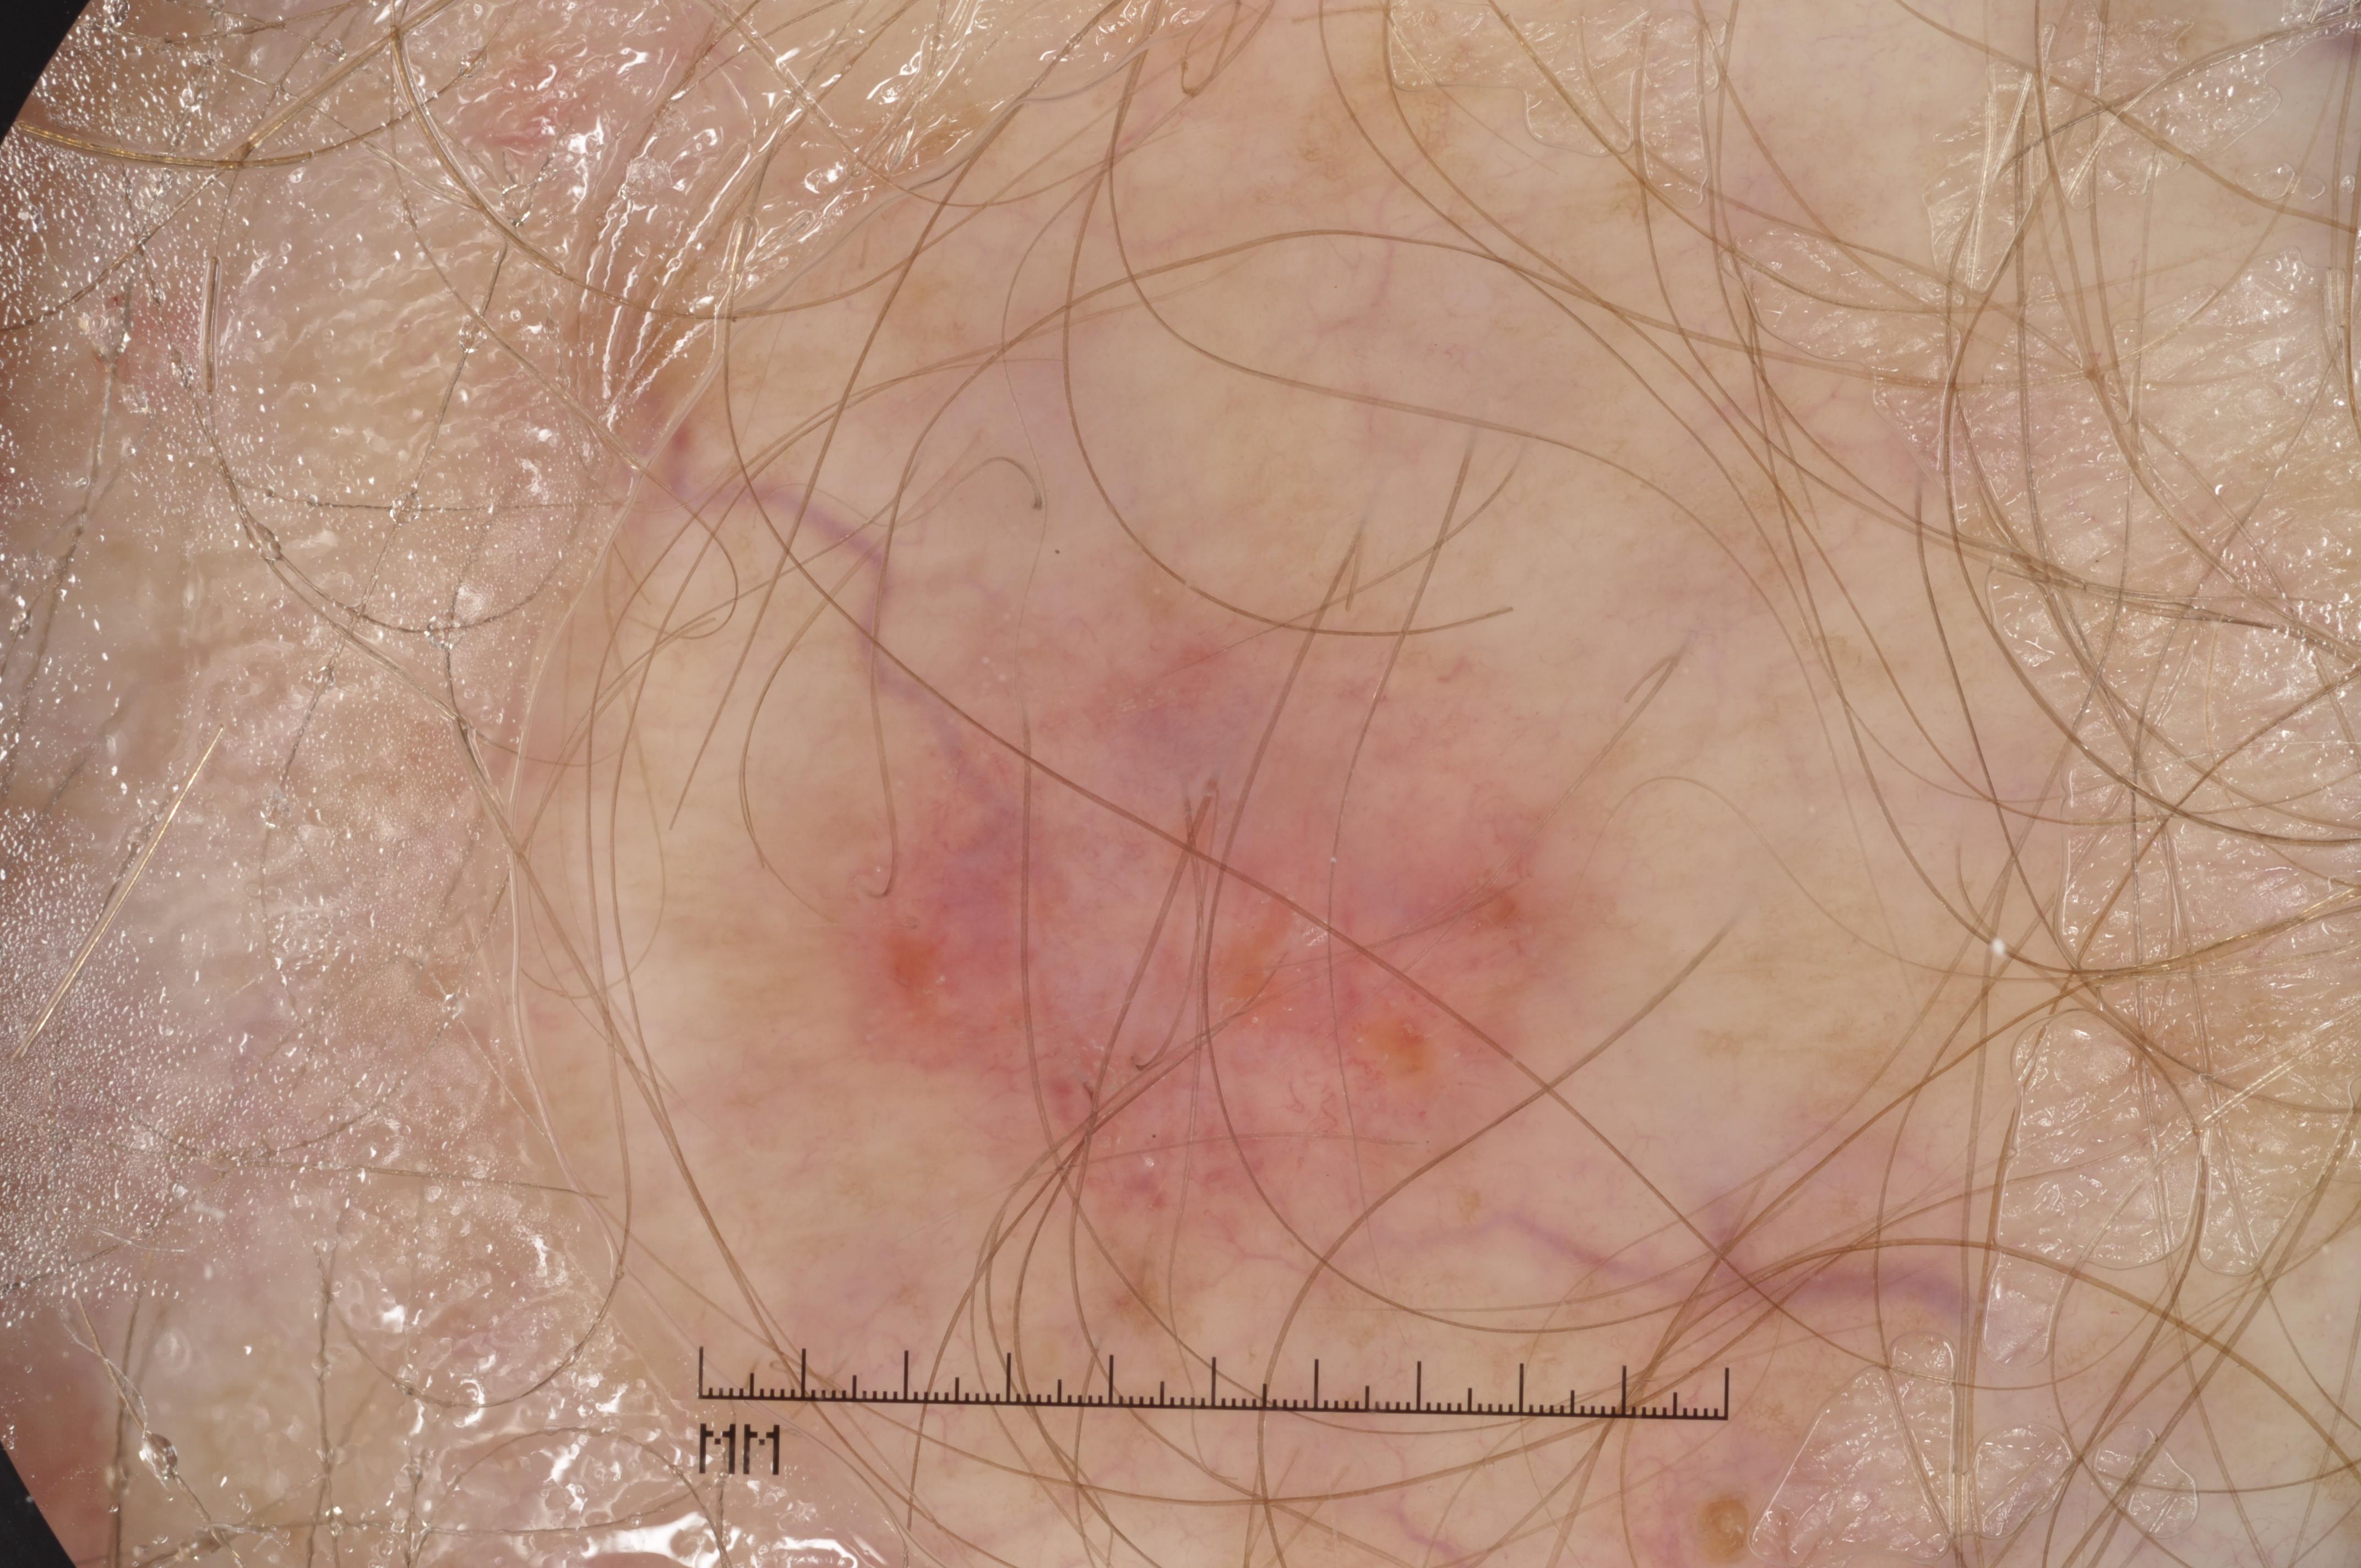

{

"age_approx": 60,

"anatom_site_general": "anterior torso",

"concomitant_biopsy": true,

"dermoscopic_type": "contact non-polarized",

"diagnosis_1": "Benign",

"diagnosis_2": "Benign epidermal proliferations",

"diagnosis_3": "Solar lentigo",

"diagnosis_confirm_type": "histopathology",

"image_type": "dermoscopic",

"lesion_id": "IL_7569897",

"melanocytic": false,

"sex": "male"

}